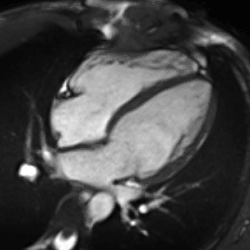

Rather, it is typically used in concert with other diagnostic techniques. In general, the clinical reasons for a CMR examination fall into one or more of the following categories: (1) when echocardiography (cardiac ultrasound) cannot provide sufficient diagnostic information, (2) as an alternative to diagnostic cardiac catheterization which involve risks including x-ray radiation exposure, (3) to obtain diagnostic information for which CMR offers unique advantages such as blood flow measurement or identification of cardiac masses, and (4) when clinical assessment and other diagnostic tests are inconsistent. Examples of conditions in which CMR is often used include tetralogy of Fallot, transposition of the great arteries, coarctation of the aorta, single ventricle heart disease, abnormalities of the pulmonary veins, atrial septal defect, connective tissue diseases such as Marfan syndrome, vascular rings, abnormal origins of the coronary arteries, and cardiac tumors.

Enlarged right ventricle with poor function in a patient with repaired tetralogy of Fallot by CMR